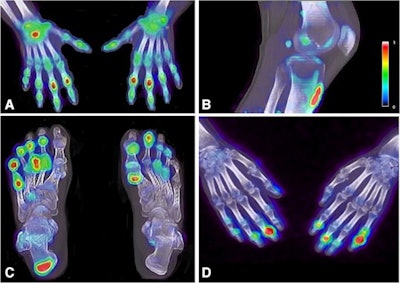

F-18 NaF enhancement in the right wrist and proximal interphalangeal joints of the hands (A), at the patella tendon insertion (B), in the metatarsophalangeal and interphalangeal joints of the feet and the right Achilles tendon (C), and in the distal interphalangeal joints of the hands (D). Image courtesy of the European Journal of Nuclear Medicine and Molecular Imaging.According to the study results, 81.8% of PET-positive joints were missed on clinical assessment. The team found that only 18.2% of PET-positive joints were clinically positive (that is, tender or swollen). But most PET-negative sites were also clinically negative (611/638). Similar results were found for entheses, with 70.5% of the PET-positive entheses missed on clinical evaluation and 29.5% of PET-positive entheses clinically identified.